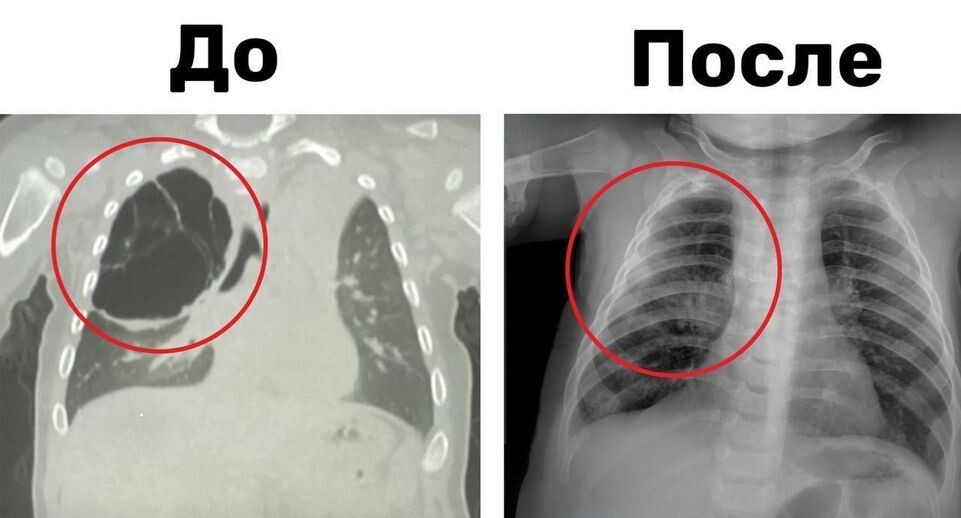

Врачи Детского клинического центра имени Л. М. Рошаля спасли восьмимесячного ребенка с кистой в правом легком. Образование нашли во время воспалительного процесса, который развился у юного пациента на фоне острой респираторной вирусной инфекции. Киста достигла 15 сантиметров в длину, заполнила часть верхней доли легкого и сдавила здоровую ткань органа ребенка. «Мы выполнили ему торакоскопическую операцию: без разреза нам удалось аккуратно удалить кисту вместе с пораженной частью верхней доли правого легкого», — пояснил заведующий отделением детской хирургии № 2 Никита Степаненко. По словам врача, вмешательство длилось около часа. После успешно проведенной операции и положенного периода восстановления юного пациента выписали. Автор: Елизавета Теличенко

Киста достигла 15 сантиметров в длину, заполнила часть верхней доли легкого и сдавила здоровую ткань органа ребенка.

«Мы выполнили ему торакоскопическую операцию: без разреза нам удалось аккуратно удалить кисту вместе с пораженной частью верхней доли правого легкого», — пояснил заведующий отделением детской хирургии № 2 Никита Степаненко.